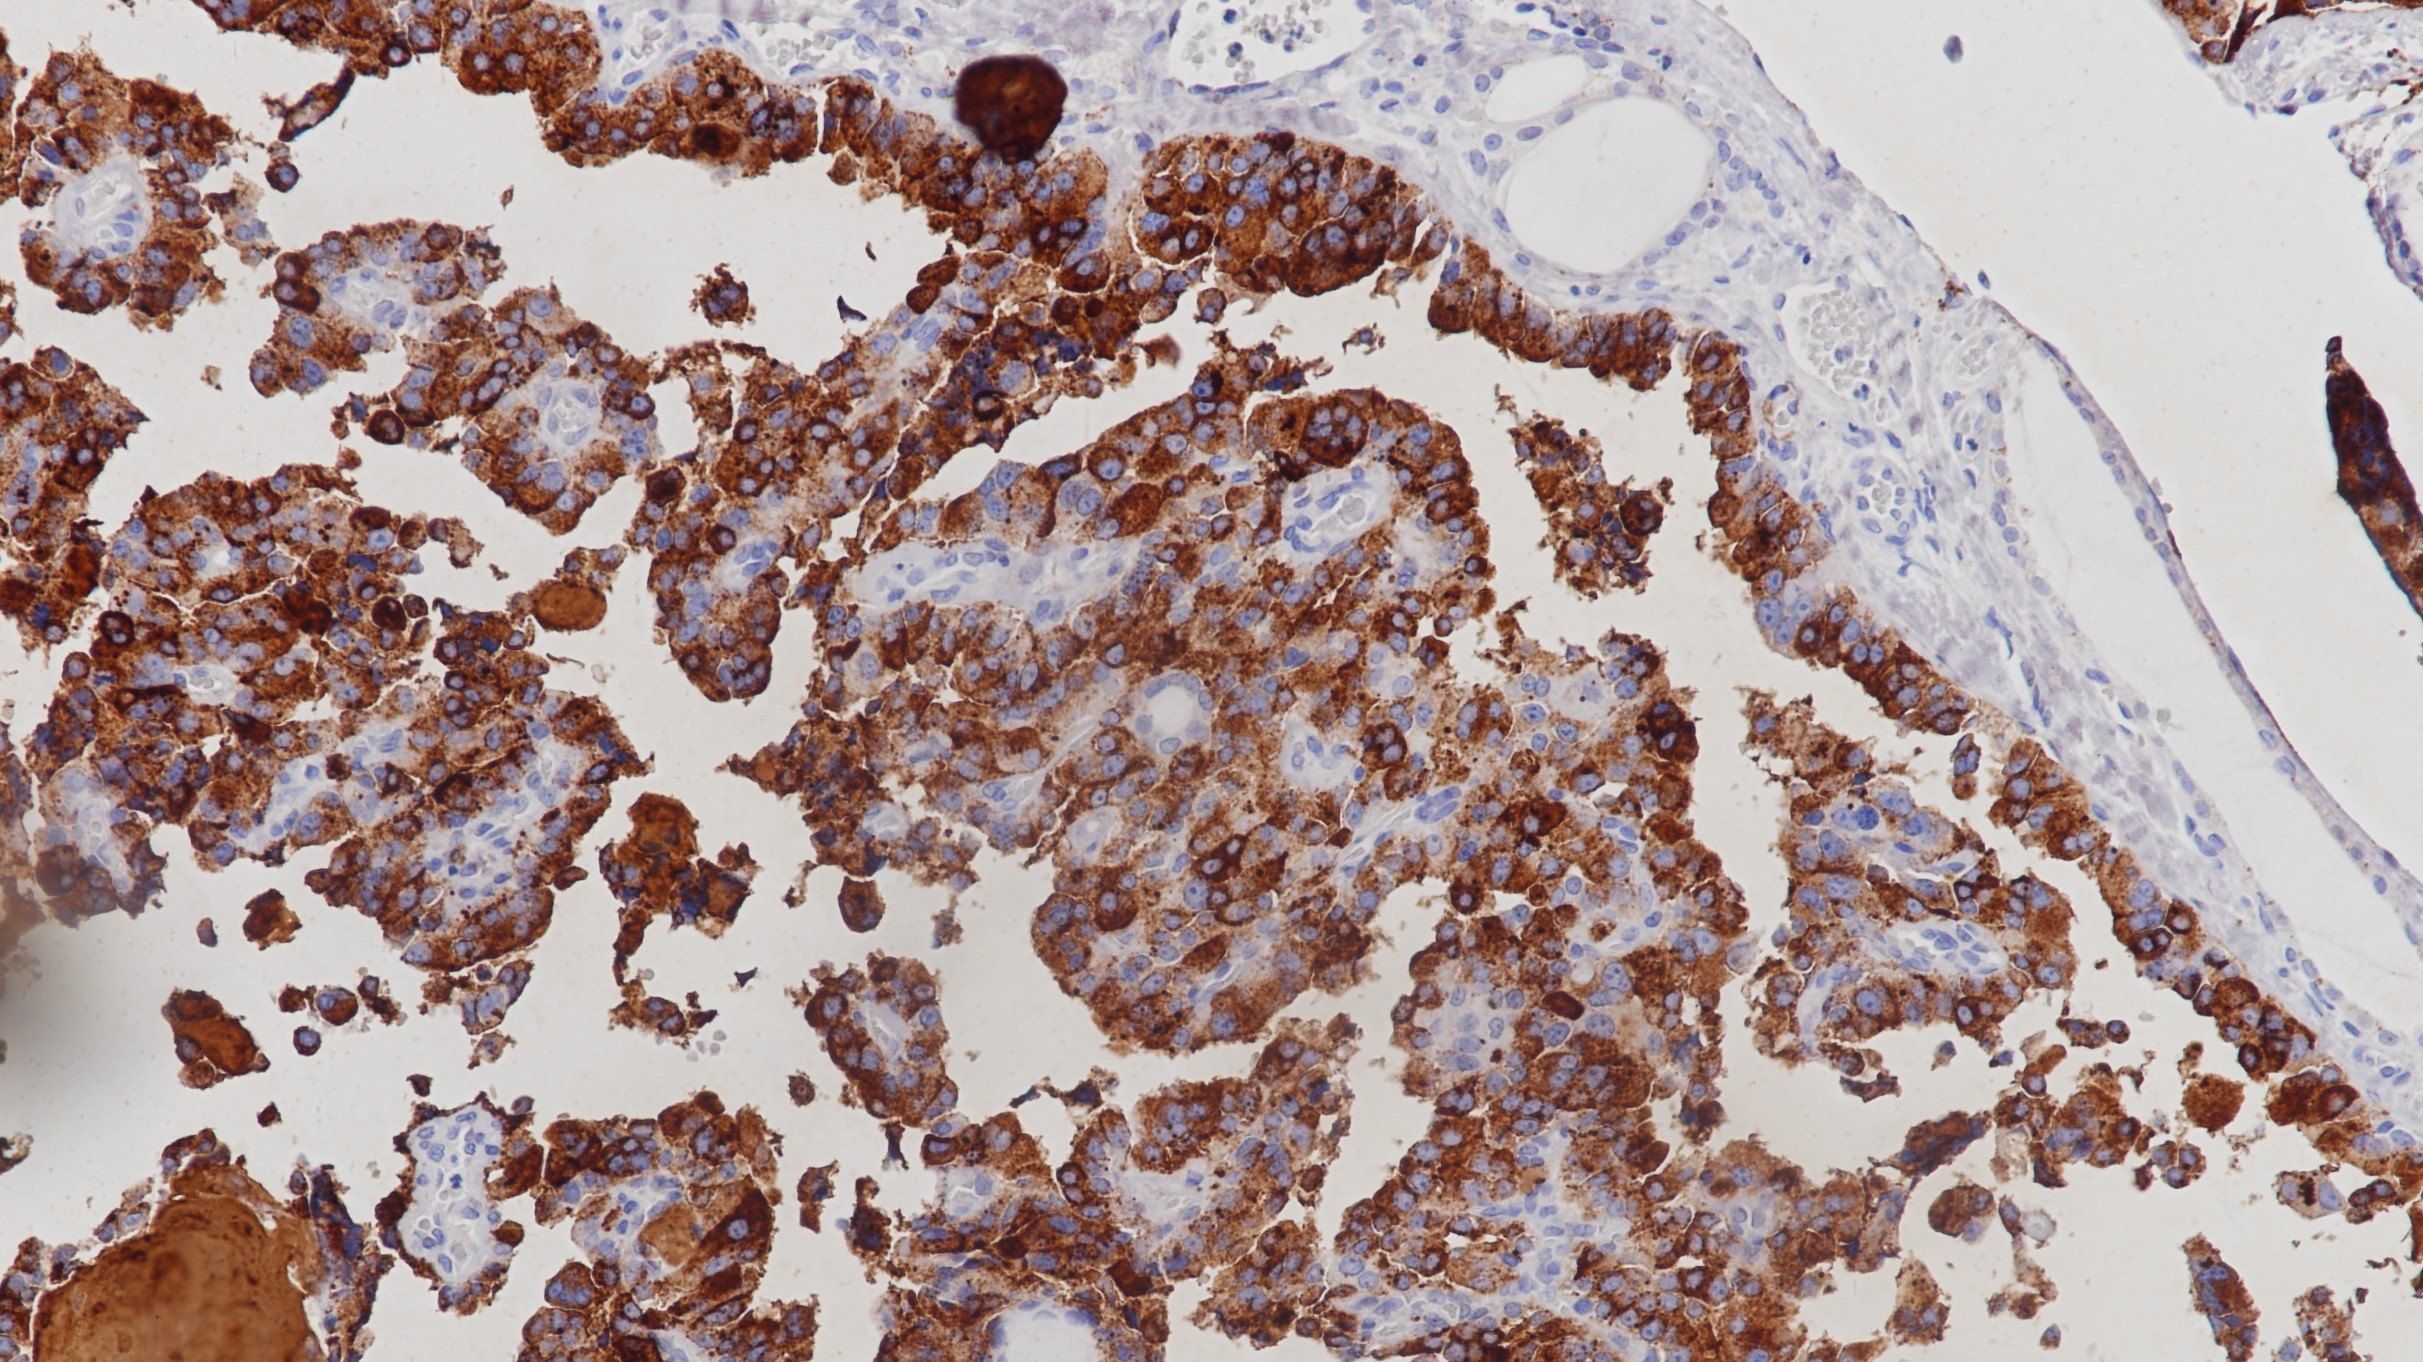

2.Rathore AS, et al. CD3+, CD4+ & CD8+ tumour infiltrating lymphocytes (TILs) are predictors of favourable survival outcome in infiltrating ductal carcinoma of breast. Indian J Med Res. 2014 Sep;140(3):361-9.